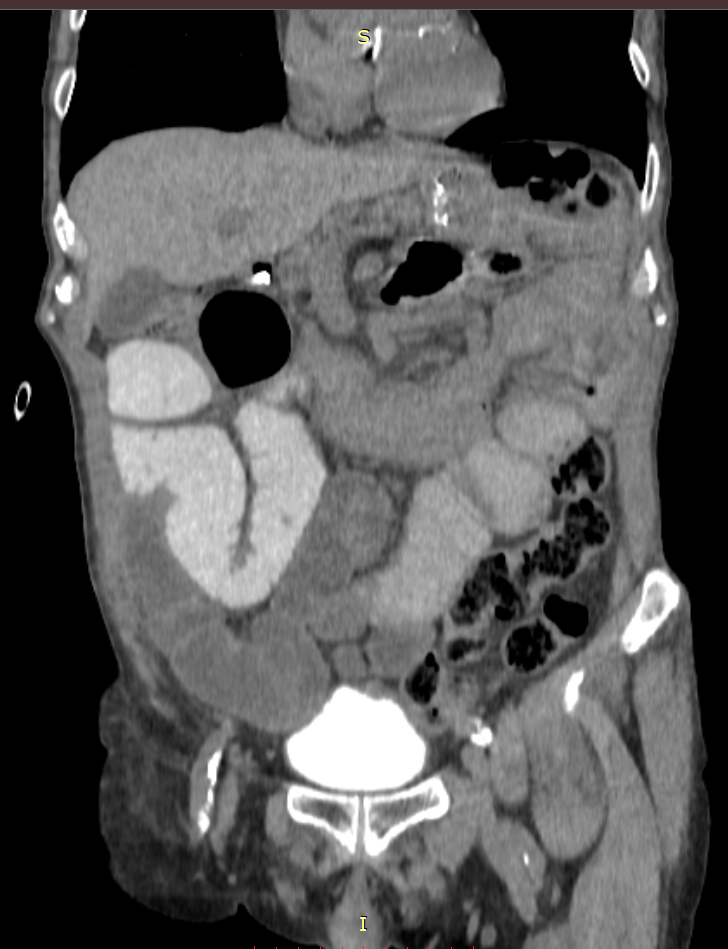

У пациента по данным КТ выявлена острая спаечная тонкокишечная непроходимость без явлений нарушения кровоснабжения тонкой кишки.

В таких случаях возможно начало лечения без операции, к тому же у пациента при обследовании выявлены тяжелые нарушения электролитов крови. Все это диктовало необходимость быстрого начала интенсивной терапии, что уже было начато в отделении экстренной помощи и далее продолжено в хирургическом отделении. В процессе интенсивной терапии и при дополнительном обследовании стало понятно, что пациенту необходимо оперативное вмешательство, которое было выполнено по стабилизации гомеостаза.

Операция выполнена лапароскопическим доступом, операционная бригада: Устименко А.В., Елизарова Н.И. Во время операции установлено, что причиной непроходимости явилась спайка, которая вызывала сдавление просвета тонкой кишки. Выполнено рассечение спайки, что послужило успешному разрешению кишечной непроходимости. Далее непродолжительный послеоперационный период, который проходил без осложнений, и выписка пациента на амбулаторный этап лечения.